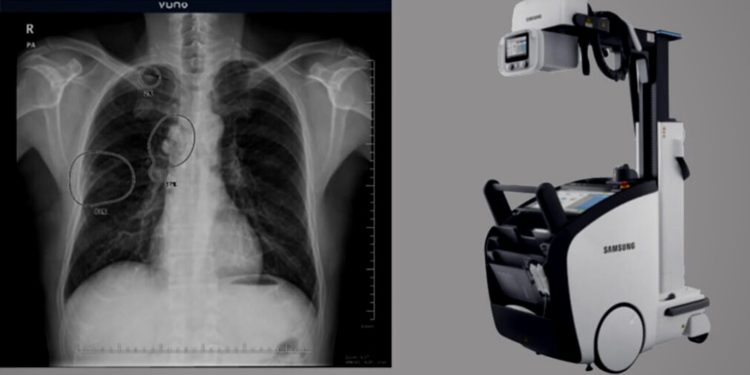

VUNO Inc, the South Korean AI medical solutions firm, has signed a contract with Samsung Electronics Co. Ltd to develop an X-ray diagnostic solution. The Samsung-manufactured GC85A diagnostic device will have VUNO’s AI-powered functions to offer a better radiography system.

The duo had come together in June for a different contract that worked on similar AI-powered medical equipment. Following their last contract, their Med-Chest X-ray solution is made available in Korea, Europe, and several other parts of the world. After embedding a mobile digital radiography system in Samsung’s GM85, VUNO has partnered with the South Korean tech giant for another contract signed last week.

The Med-Chest X-ray device developed by Samsung and AI-powered by VUNO works on areas prone to various pulmonary diseases. It accurately recognizes the thoracic dysfunction through chest radiographs. With this, the system essentially helps healthcare providers detect such areas for the diagnosis of pneumonia and tuberculosis.

While discussing the development of the new product, a VUNO official said that the clinicians could easily get the Med-Chest X-ray solution integrated with many of their X-ray equipment. It is due to the AI algorithms that have managed to reduce model weight by optimizing the computations.

As a result, the Med-Chest X-ray solution enables quick data processing in both CPU and GPU environments. With this, the results examined through artificial intelligence can be easily seen while X-rays are run.